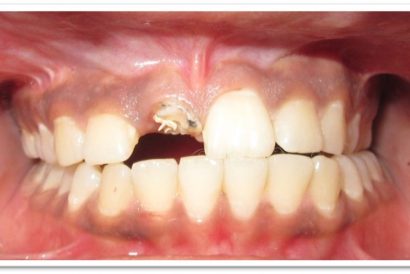

Patient Name: Poonam Joshi

Tooth Involved : 21

Diagnosis : Hypoplastic Stains With 21

Treatment : Direct Composite Using Nanohybrid Composite

Stains Masked Using IVOCLAR EMPRESS COLOUR White And Honey

Before

After